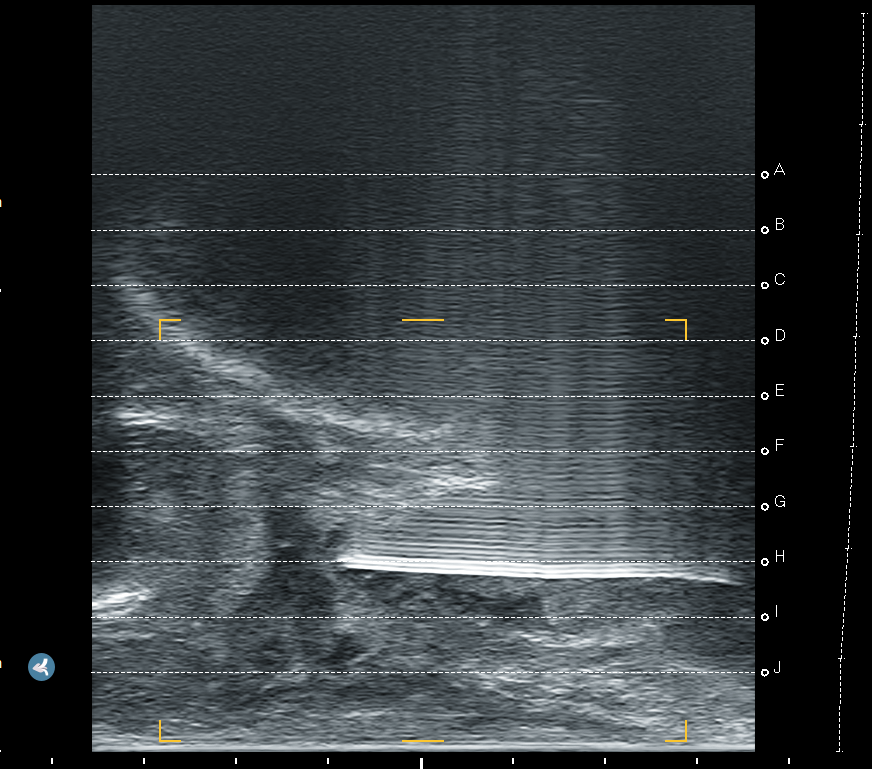

We prospectively assessed the tolerability and operational effectiveness of transperineal MRI-targeted biopsies under pure local anaesthesia with a prospective, monocentric, mono-operator cohort of transperineal prostate biopsies. Patients were assigned for biopsies according to clinician decision following the “MRI pathway” [5] from our urological consultation in Godinne University Hospital (Yvoir, Belgium). This study was conducted between late January 2024 and late May 2024. The decision for local anaesthesia or sedation was made after discussion between the patient and the urologist, aiming to assess our current process of selection for biopsies. Out of 51 patients, 34 received local anaesthesia, whereas 17 opted for sedation. The prostate biopsies took place in a daycare clinic operative room, with the help of 1 nurse. If the biopsy was performed under sedation, an anaesthesiologist was present. Sedation was performed using propofol. No fasting was required for patients under local anaesthesia, whereas patients undergoing sedation had to observe a 6 h fast. All of our biopsies were performed transperineally, with image-based MRI-US elastic fusion using the Koelis Trinity® platform (Koelis, Meylan, France), and following the MUSIC (Michigan Urological Surgery Improvement Collaborative) pattern. We targeted 3–4 biopsy cores for each MRI target lesion with a PIRADS score ≥4 or a PIRADS score of 3 with PSA density > 0.15 ng/mL/cc. In case of a mix of PIRADS 4–5 and 3 lesions, only PIRADS 4–5 were targeted. A preoperative urine analysis was performed to rule out bacteriuria. No antibiotic prophylaxis was used based on recent RCT [17] and local experience. The patient was placed in the lithotomy position and asked to self-retract the scrotum with the hands. We used cutaneous disinfection with a povidone–iodine solution and performed local anaesthesia with 20 mL Linisol 2% diluted with 20 mL NaCl 0.9%. We first performed a superficial anaesthesia with 20 mL of anaesthetic solution with a 21 G needle in a fan-shaped pattern from the median raphe down to each side to the anal margin (Figure 1). After the superficial anaesthesia, we performed MRI contouring on the Koelis Trinity® software Promap 4.3.0. Then we performed prostatic/deep anaesthesia under transrectal ultrasound control with 10 mL of anaesthetic solution for each side, targeting the posterior–apical plane with the outer shaft of an 18 G biopsy needle (Figure 2). Once both superficial and prostatic anaesthesia were performed, transrectal ultrasound image acquisition, contouring, and image fusion were performed. After a short waiting period, prostate biopsies were performed using a 22 cm 18 G coaxial needle and a BD Magnum™ biopsy gun (Becton, Dickinson and Company, Franklin Lakes, NJ, USA).

Figure 2. Prostatic anaesthesia.